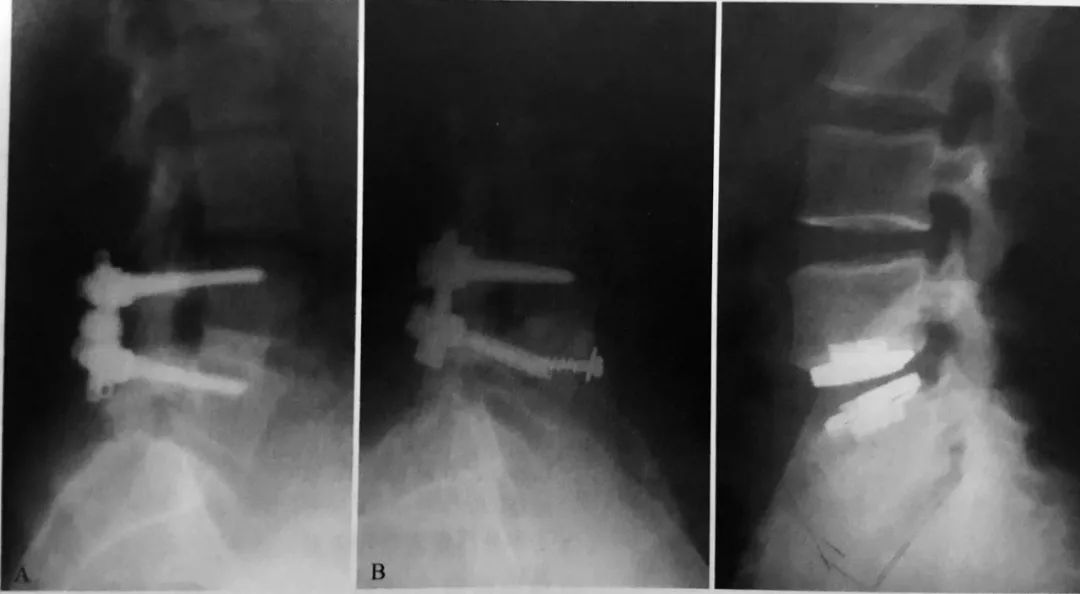

A后路椎间融合手术,采用椎体间异体皮质骨移植联合后路内固定和融合手术 B 前路椎体间融合,采用异体股骨移植结合后路内固定融合手术 C 人工椎间盘置换术